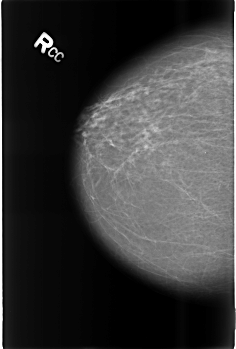

Digital Database for Screening Mammography

Volume: benign_14 Case: B-3467-1

B_3467_1.RIGHT_CC

DENSITY 2

RIGHT_CC LINES 4536 PIXELS_PER_LINE 3056 BITS_PER_PIXEL 12 RESOLUTION 50 NON_OVERLAY